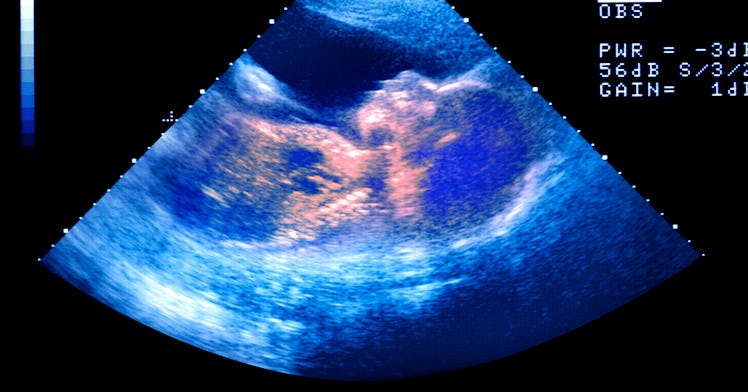

Parents who can’t wait to find out their baby’s gender have options. Ultrasounds. Bloodwork. Amniocentesis. But many expecting moms and dads prefer to be surprised, which inevitably leads to a lot of “educated” guesses, most of which will be based on persistent myths and wives' tales. Old and wrong ideas about gender determination hold so much sway that people are constantly doing ridiculous things: Women pee in Draino and men consult the Chinese calendar or measure bumps. While most of this is harmless–and maybe even fun–it’s also important to retain perspective and understand that many of the “old-fashioned” means of determining sex are complete nonsense. That said, many does not mean all.

Even before your first ultrasound, your doctor will likely use a doppler heart monitor to measure your baby’s heart rate. If all is well, the heart rate should fall between 120 and 160 beats per minute. But ask around, and you’ll find that many people believe a heart rate closer to 160 means you’re going to have a girl, while a heart rate closer to 120 means you’re having a boy.